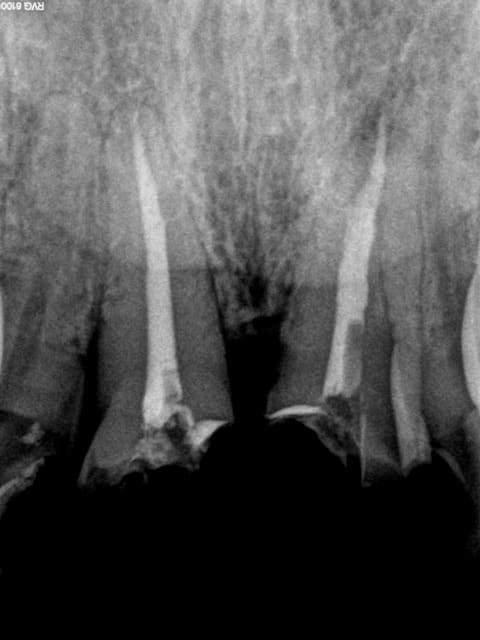

> tailles sous gingivales sur dents vivantes : est-ce justifié sur une molaire ?

Ca dépend du volume d'ancien matériau que t'as dégagé, des infiltrations sous ces dites obturations, etc...C'est pas un dogme, mais en reconstituant on se donne souvent bonne conscience grace à la hauteur du moigon. Sur DV tu peux pas tricher.

Endos sans digue, avec de la carie résiduelle, la gutta/ciment ne remplit pas toute la lumière du canal, pas de respect de l'espace biologique, effet férule minimaliste.....

Vu les autres dents le patient ne mérite peut être pas mieux et l'indication est là mieux posée, mais tu te positionnes comme un pro de l'endo puisque tu en ferais souvent et là, c'est pas flagrant...